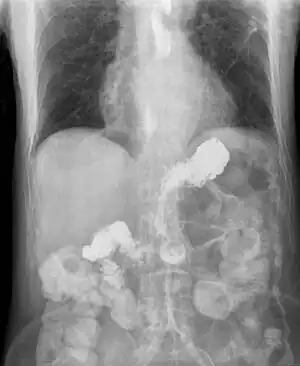

X-ray showing radiocontrast from the stomach (white material below diaphragm) entering the esophagus (three vertical collections of white material in the mid-line of the chest) due to severe reflux